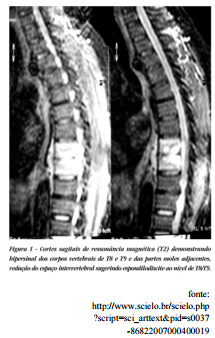

A imagem a seguir retrata um exemplo de tomografia de:

Coluna